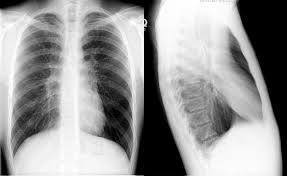

Chest x ray hyperinflation definition. Narrowing of the transverse cardiac diameter felson s principles of chest roentgenology by lawrence goodman states that when the right hemidiaphragm lies below the 10th posterior rib it is diagnosed as hyperinflation. Chest x ray definition a chest x ray is a procedure used to evaluate organs and structures within the chest for symptoms of disease. Airways difficult to see hyperinflation bilateral 9 posterior ribs reduced vascular markings flat diaphragms small heart unilateral 9 posterior ribs reduced vascular markings flat hemi diaphragm herniation of lung. In some cases however the lungs may appear hyperinflated on a chest x ray for reasons that have nothing to do with lung function.

It happens when you can t exhale or push out all of the air that s in your lungs the air gets trapped and takes up. If it isn t clear what s causing the hyperinflation your doctor might recommend additional testing such as a computerized tomography ct of the chest and pulmonary function tests. Increases heart size 3. Hyperinflated lungs are present in many chronic chest conditions in particular copd and asthma.

A chest x ray is the most common tool used to diagnose hyperinflation of the lungs. Chest x rays include views of the lungs heart small portions of the gastrointestinal tract thyroid gland and the bones of the chest area. Small lung volumes 2. More than 6 anterior or 10 p.

In some cases lungs can appear hyperinflated on x rays for reasons unrelated to lung function. Enlargement of retrosternal space on lateral chest x ray 5. The radiologist will likely take images both during inspiration and expiration. Lung hyperinflation is a common feature of patients with chronic obstructive pulmonary disease copd it is also linked to aging and other chronic diseases that cause airflow obstruction.

X rays are a form of radiation that can penetrate the body and produce an image. This may be evidenced by. Hyperlucent lungs less bronchovascular markings per cm2 c. Often however the condition is detected incidentally meaning that lung hyperinflation was noticed on an imaging test done for another reason.